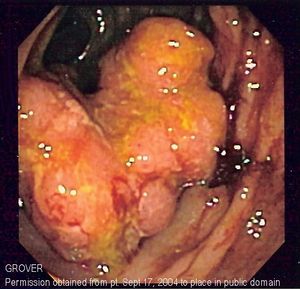

تنظير القولون

- تنظير القولون: يستخدم تنظير القولون أنبوبًا طويلاً ومرنًا ورفيعًا يتصل بكاميرا فيديو وشاشة لعرض القولون والمستقيم بأكملهما. إذا تم العثور على أي مناطق مشتبه في إصابتها بالمرض، يمكن للطبيب تمرير الأدوات الجراحية من خلال أنبوب لأخذ عينات من الأنسجة (خزعات) لتحليلها وإزالة السلائل.